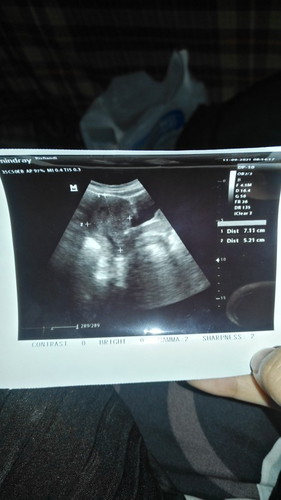

saya memiliki riwayat keguguran saat kehamilan pertama, itu karna janin tidak berkembang, lalu saat ini saya sedang mengandung lagi usia kandungan 12w , sudah seminggu saya pendarahan , meski pendarahan ringan tapi mengkhawatirkan kan bun :( , itu selesai hb, pertama keluar darah segar merah tidak terlalu banyak, besoknya ternyata masih keluar sedikit, besoknya berhenti besoknya lagi keluar sedikit besoknya berhenti, besoknya keluar lendir merah , kesini kesini berenti darahnya tapi malah keluar lendir merah sedikit sekali, hanya berupa tetesan, saya seminggu sebelumnya memeriksakan diri saya ke bidan dan menceritakan keluhan saya, tapi bidan tidak ada tindakan apa apa hanya memberikan asam folat saja padahal saya juga dirumah selalu meminum asam folat yg dibeli di apotek, lalu kata bidan seminggu lgi kesini lagi untuk usg kebetulan juga ada jadwal usg, lalu saat usg kondisi saya masih pendarahan/flek sedikit, saat di usg kata dokter ini seperti rahim biasa, tidak ada janin nya, coba ditespack ulang katanya, saya di tespack ulang lgi di sana, namun saat di tespack saya masih positif hamil, tapi hasil usg kosong tidak apa apa, khawatir juga karna saya sudah pendarahan seminggu, lalu saat selesai saya pulang, tidak dikasih obat apapun, saya bertanya kepada bidannya, apakah ada obat penguat bu atau obat pemberhenti pendarahan untuk kandungan saya, kata bidan nya ngga , ngga dulu katanya, lalu saya pulang, saya heran kenapa tidak ada tindakan apapun, padahal saya ada keluhan , saya pulang hanya membawa tespack dan hasil usg saja, #seriusnanya #bantusharing #pleasehelp